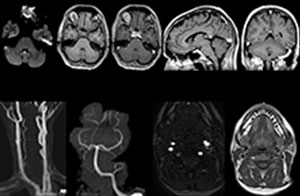

A range of protocol sheets was developed to help ensure that referring physicians order the most appropriate MRI exam. The optimized MRI protocols also include 3D contrast-enhanced imaging, allowing neurosurgeons to comfortably use the isotropic data in the operating room while performing stereotaxic surgery.

For Dr. Karis, the next goals for the neuro ED include converting the exams for acute stroke and TIA patients from CT to MRI, offering an alternative management option for these patients. Also, collaboration between other departments is currently underway, encouraging the performance of targeted exams with the ED MRI. These improvements in workflow and faster turnaround times may result in further reductions in scanning time.